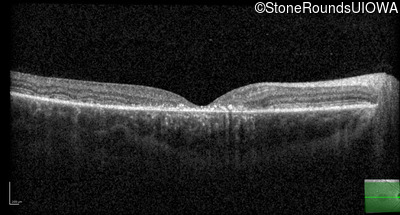

| AR Stargardt Disease | ABCA4 | IVS21-2 A>G | Pro1380Leu CCG>CTG | AR |